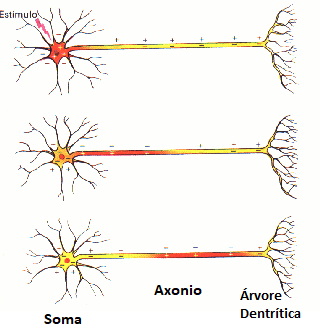

Os Neurônios são as células excitáveis do tecido nervoso (que constituem o encéfalo e medula espinhal, gânglios e nervos do reino animal) e com já vimos são capazes de gerar PA. Um potencial de ação pode assumir diversos formatos, mas ao longo do axônio (Figura 1) de um neurônio eles tendem a uma curva como a da Figura 2.

- O período que contém a repolarização e hiperpolarização da membrana é chamado período refratário, e se caracteriza por não permitir que ocorra nenhum disparo até que a membrana atinja o potencial de repouso.

Nas animações das figuras 12 e 13 vemos a evolução espacial do potencial elétrico com o decorrer do tempo. Na figura 12, o estímulo inicial está abaixo do limiar de voltagem, desta forma ele não gera um PA e a célula volta rapidamente para o seu PR. Na figura 13 o estímulo inicial está acima do limiar, logo um PA é gerado e o pulso elétrico é propagado ao longo do axônio.